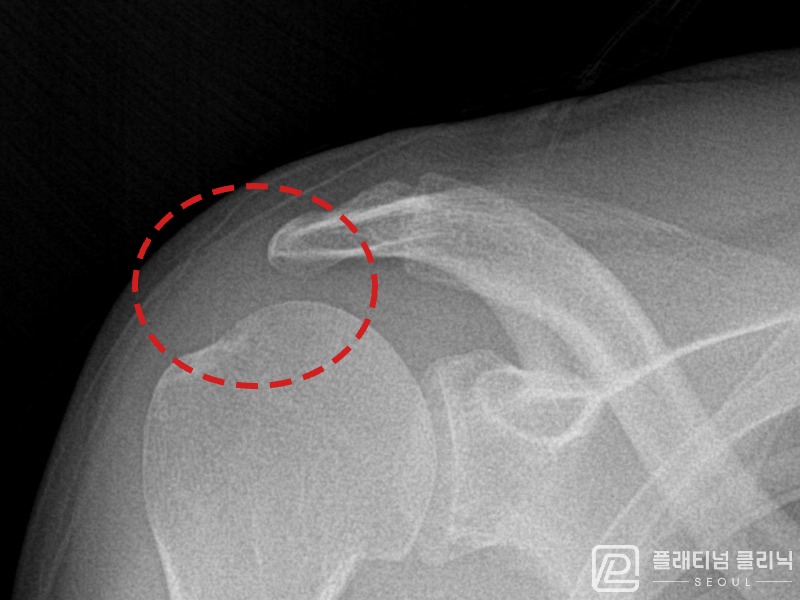

[촬영시기:21.08.30~21.09.09]

[석회분쇄흡입술] 우측 어깨 통증으로 밤잠을 못 이루고 팔을 올리기 어려워진 30대 여성 환자로, X-ray에서 우측 극상근건 내 석회 침착이 확인되어 석회분쇄흡입술을 시행하였습니다.